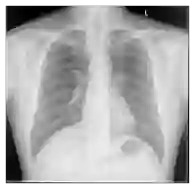

Recent advances in general medical AI have made significant strides, but existing models often lack the reasoning capabilities needed for complex medical decision-making. This paper presents GMAI-VL-R1, a multimodal medical reasoning model enhanced by reinforcement learning (RL) to improve its reasoning abilities. Through iterative training, GMAI-VL-R1 optimizes decision-making, significantly boosting diagnostic accuracy and clinical support. We also develop a reasoning data synthesis method, generating step-by-step reasoning data via rejection sampling, which further enhances the model's generalization. Experimental results show that after RL training, GMAI-VL-R1 excels in tasks such as medical image diagnosis and visual question answering. While the model demonstrates basic memorization with supervised fine-tuning, RL is crucial for true generalization. Our work establishes new evaluation benchmarks and paves the way for future advancements in medical reasoning models. Code, data, and model will be released at \href{https://github.com/uni-medical/GMAI-VL-R1}{this link}.